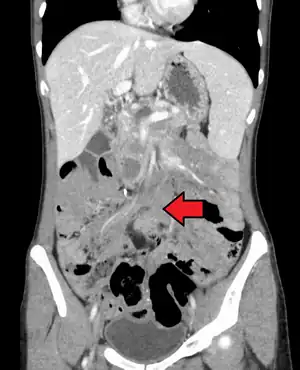

Desmoid tumor as seen on CT scan

Aggressive fibromatosis or desmoid tumor is a rare condition. Desmoid tumors arise from cells called fibroblasts, which are found throughout the body and provide structural support, protection to the vital organs, and play a critical role in wound healing. These tumors tend to occur in women in their thirties, but can occur in anyone at any age. They can be either relatively slow-growing or malignant. However, aggressive fibromatosis is locally aggressive and can cause life-threatening problems or even death when they compress vital organs such as intestines, kidneys, lungs, blood vessels, or nerves. Most cases are sporadic, but some are associated with familial adenomatous polyposis (FAP). Approximately 10% of individuals with Gardner's syndrome, a type of FAP with extracolonic features, have desmoid tumors.[1]